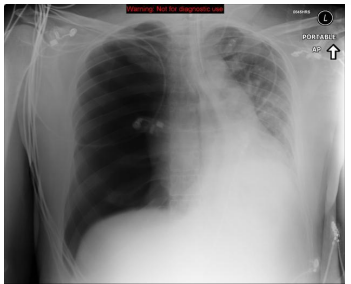

Um paciente vítima de politrauma é trazido para a sala de emergência com dispnéia, apresentando este Rx de tórax. Qual o principal diagnóstico do exame?